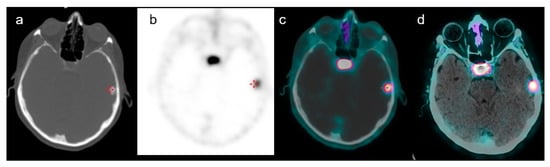

3. Results